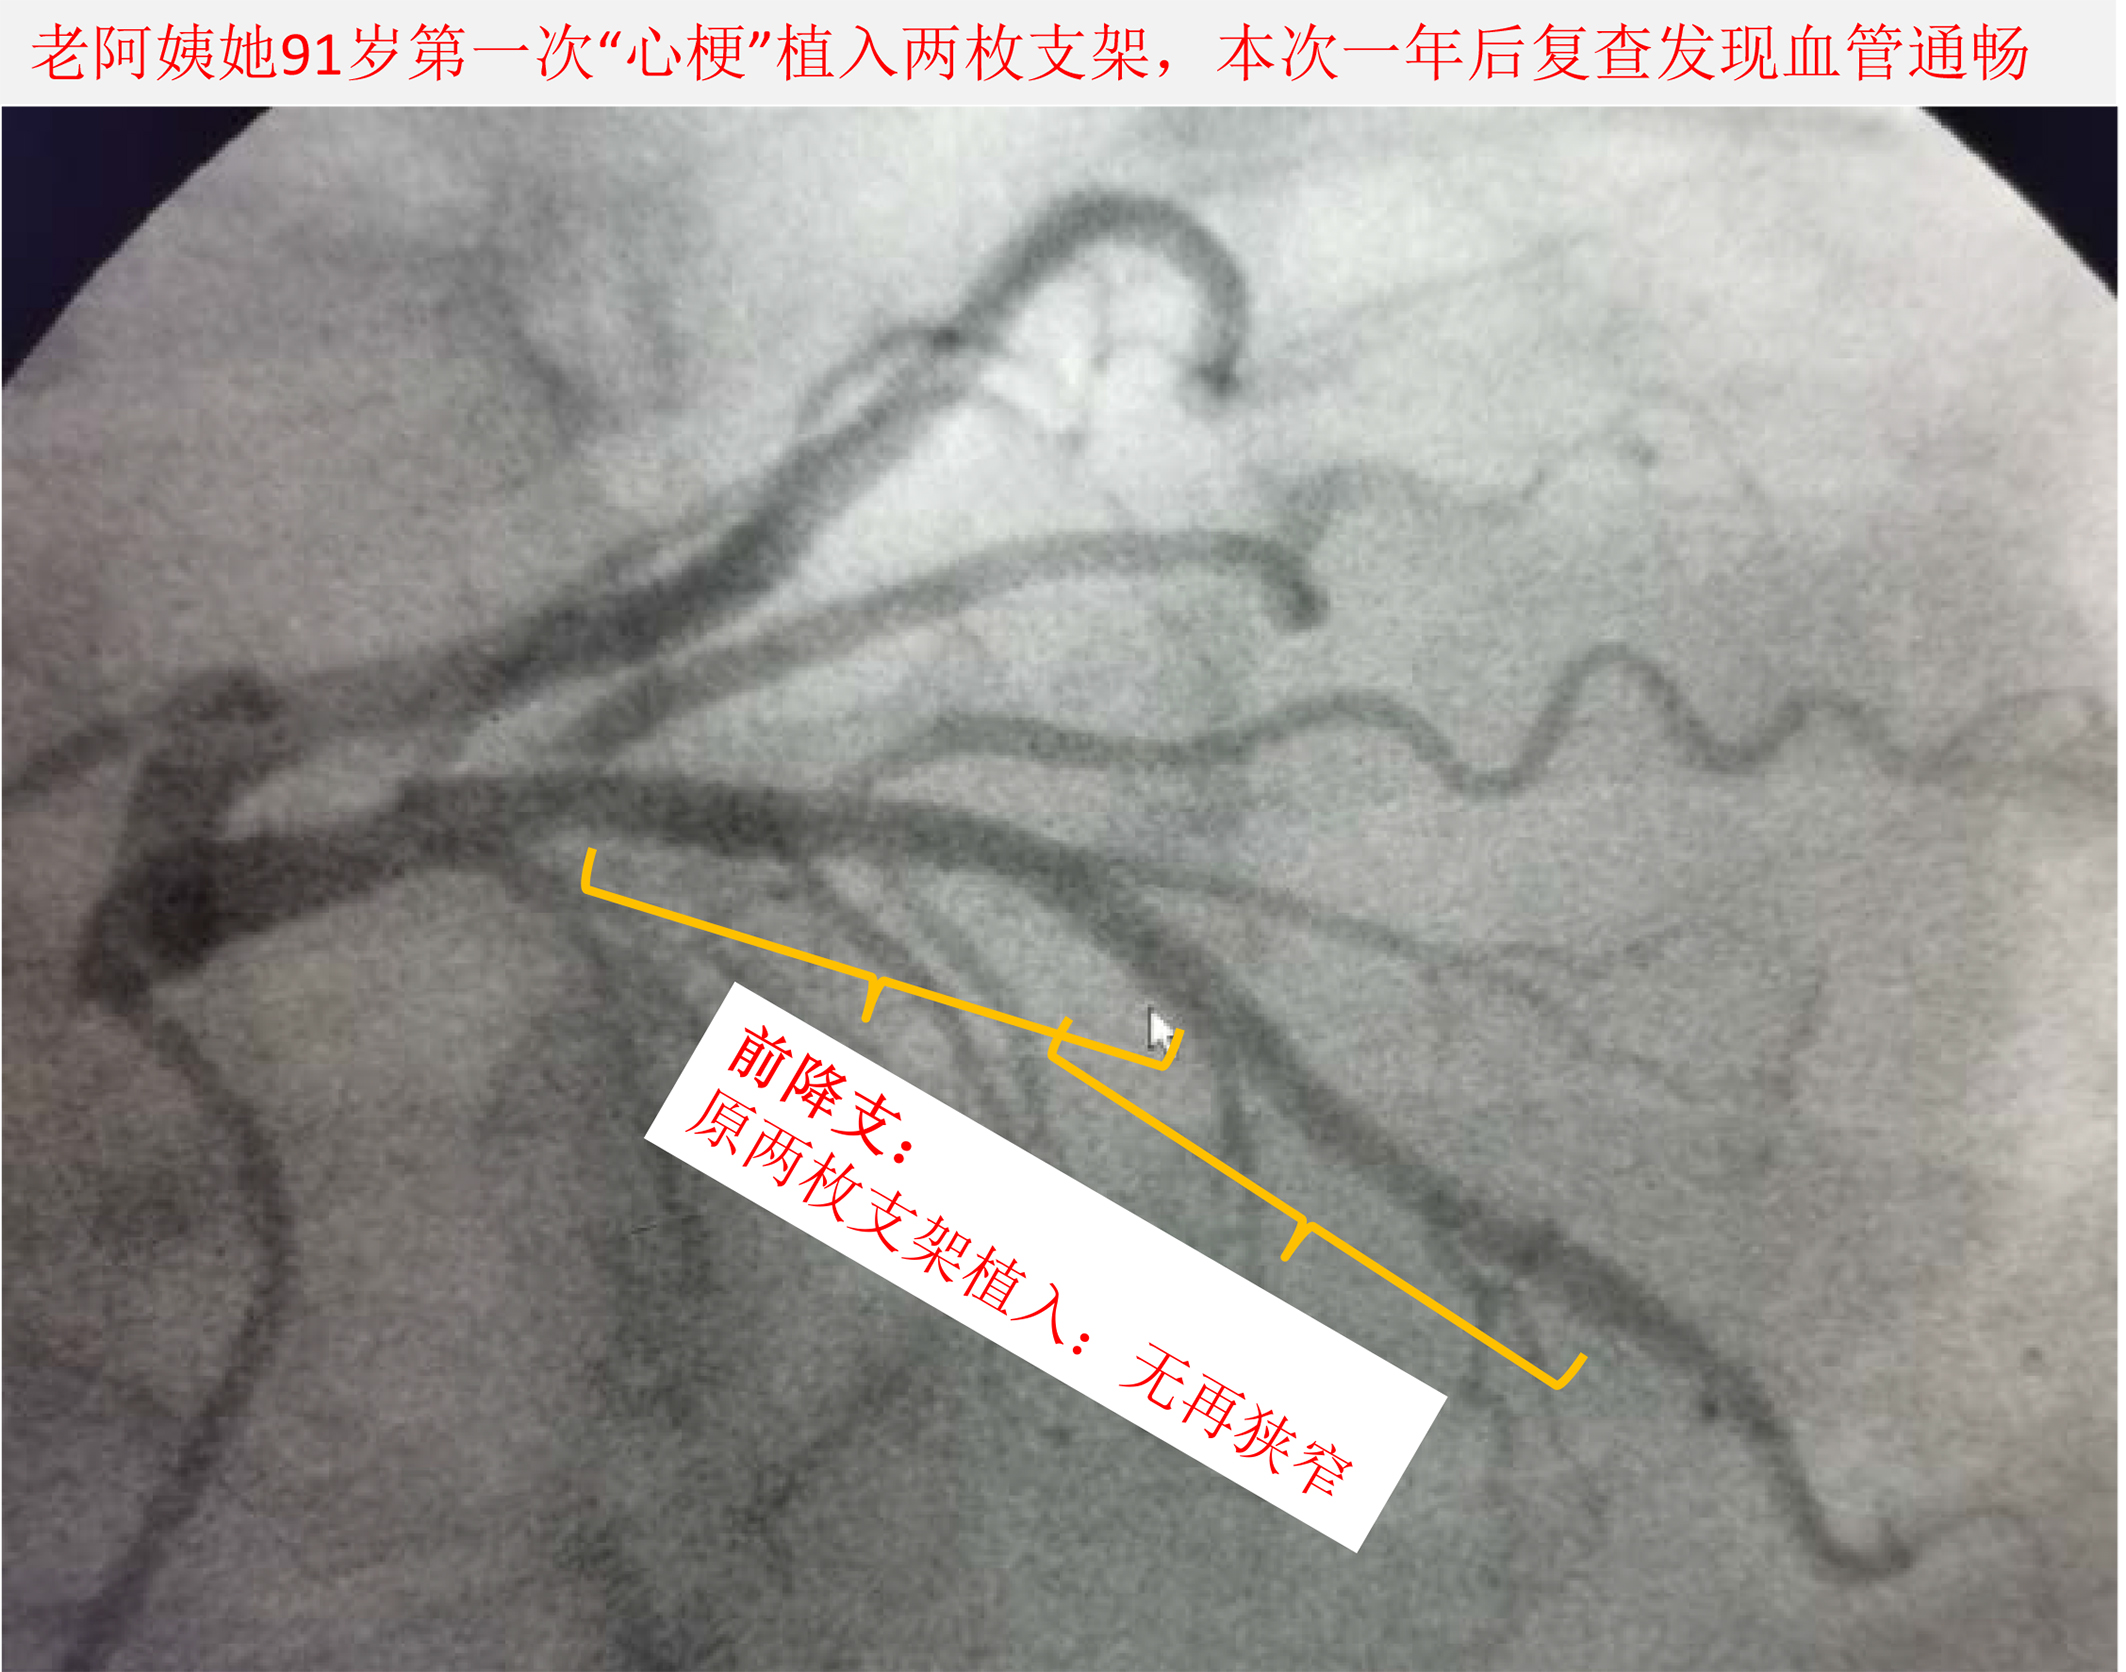

图2 患者在她90岁第一次心梗,在前降支植入两枚支架,本次复查血管通畅,支架效果好。

我们再次给患者复查了心脏造影,提示一年前装的两枚支架效果挺好,这次另外一支心脏大动脉出现了高度狭窄基础上的急性破裂,是导致这次心梗的“罪犯血管”,并且病变处理难度不大。而这处病变若不处理可能存在反复心绞痛、再发心梗可能。我们考虑植入支架的获益明显大于不处理。经患者本人及家属同意后,如预料般仅花数分钟即重建了血管。术后患者同时经过积极的优化的中西医药物治疗后情况进一步好转,出院前可在病房下地活动了。